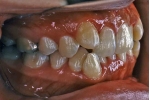

日本矯正歯科学会専門医課題症例(第4症例)

カテゴリー:ClassⅡ division 2 malocclusion (Overbite 5mm以上; 抜歯症例)

| マルチブラケット終了時